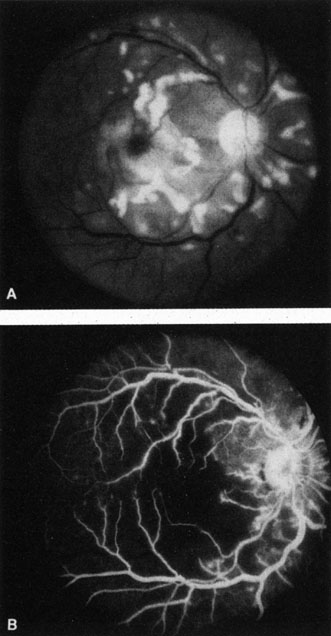

When a branch retinal artery is obstructed, there is usually whitening of the retina in the area supplied by the artery (Fig. 2). In most eyes (62% in one series), emboli are responsible for the obstruction.94 The temporal branch arteries are involved in almost all cases that have been reported,92,94 but whether this is because nasal branch retinal artery obstructions are rare or because such obstructions are simply asymptomatic is unknown. The characteristics of a branch retinal artery obstruction on intravenous fluorescein angiography are similar to those for central retinal artery obstruction.

Fig. 2. Multiple branch retinal artery obstructions in a young woman with encephalopathy and hearing loss. (Photograph courtesy of Jack W. Pierce, M.D.)

Occasionally, patients present with a bilateral branch retinal artery obstruction.94 Some have obstructive retinal arteries without evidence of systemic abnormalities,95,96 whereas others have accompanying symptoms such as deafness.97,98 Some younger patients—usually women—have been reported to have an idiopathic syndrome of branch retinal artery obstruction, encephalopathy, and hearing loss (Susac syndrome).99–104,406 The eyes on these patients are characterized by significant systemic thromboembolic events; recurrent bilateral retinal arterial occlusions; segmental arteriolar staining by fluorescein angiography, occasionally associated with periarteriolar retinal whitening or mild vitreous cells; and a predilection for vestibuloauditory or transient sensorimotor symptoms.104 Some patients, however, present with only recurrent bilateral retinal arteriolar occlusions and never develop the associated vestibuloauditory or sensorimotor systems; whether these patients have a partial manifestation of Susac syndrome is unknown. The etiology of branch retinal artery obstruction in most cases is similar to that of central retinal artery obstruction (see Table 1). Retinal diseases (such as toxoplasmosis) can also cause branch retinal artery obstruction.